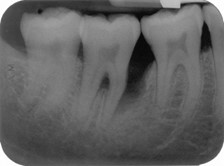

2 patterns of bone loss in this PA

horizontal and vertical

explain the development of the bone loss on the mesial aspect of the lower right second molar

• plaque present in deep pocket mesial to 47, which generates inflammation and zone of destruction causing bone loss but due to distance and thick bone between 47m and 46D a vertical bony defect created as the zone of destruction is narrower than the width of bone/space

• exacerbated due to the morphology of the mesial root – sharp curve/dilaceration and horizontal bone loss

*Thick bone between teeth more likely vertical bony defect (teeth further apart); central bone survives

Thin bone/close teeth more likely horizontal *